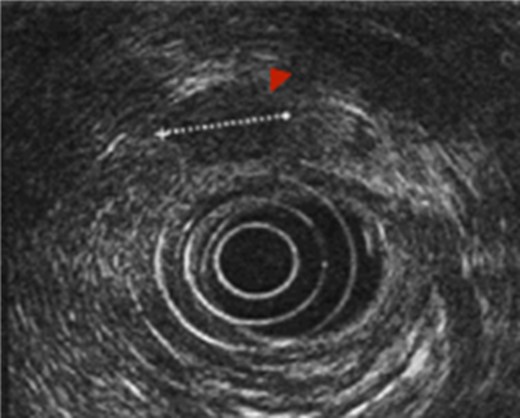

First the abdominal ultra sonography (AUS) and then CT scan revealed the presence of well-defined hypodense pancreatic head mass of 2 cm of diameter, determining bile duct and Wirsung’s duct dilatation; mesenteric vessels were clearly free of infiltration, no liver or lung suspected lesions were detected as well as volume increased lymph nodes (Fig. 1). Ecoendoscopic ultra sonography (EUS) confirmed the presence of a hypoechoic and well-defined pancreatic head mass (18 × 15 mm) and without sign of vessels infiltration (Fig. 2). A fine-needle aspiration (FNA) was performed and histopathological examination showed the presence of neoplastic cells with morphological features like the lung ones and consistent with metastasis from primary adamantinoma.

MDCT scan. (A) CT scan with well-defined hypodense pancreatic head mass of 2 cm of diameter after contrast medium intravenous injection. (B) CT scan which highlight bile duct dilatation.